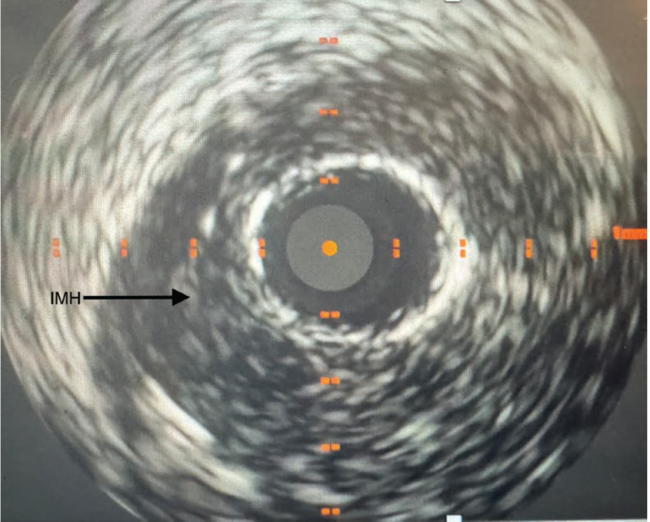

After failing to cross the lesion with a workhorse wire, a Pilot 50 (Abbott) was successful. Percutaneous transluminal coronary angioplasty (PTCA) was unsuccessful in restoration of TIMI flow. Intravascular ultrasound (IVUS) showed a large intramural hematoma (IMH) in the distal RCA and severe stenosis with the presence of fibrofatty plaque through the proximal RCA (Video 1) (Figure 3). A Penumbra mechanical thrombectomy catheter was inserted and intracoronary (IC) injection revealed flow in the distal coronary bed. Mechanical thrombectomy was unsuccessful as well (Video 2), chosen in consideration of a thrombotic component contributing to this unusual STEMI. The Penumbra catheter was re-inserted, and IC 200 mcg of nicardipine was administered, which also failed. One mg of IC tPA was then injected, which restored flow (Video 3). Next, 2.75 mm x 38 mm and a 3.0 mm x 48 mm drug-eluting stents from the mid distal to the proximal RCA were successfully deployed (Video 4). Post percutaneous coronary intervention IVUS revealed well apposed and expanded stents (Video 5). The patient was discharged 2 days later on guideline-directed medical therapy. An outpatient workup for fibromuscular dysplasia was unremarkable.

Spontaneous or trauma-related coronary intramural hematoma, a subset of coronary artery dissection, is a rare, challenging, and under-recognized diagnosis constituting 1% to 4% of all MIs.1 IMH occurs with blood accumulation between the intima and media layers of the intra-arterial wall. SCAD, stress, connective tissue disorders, and iatrogenic events are the most common causes of IMH. In hemodynamically stable lesions and patients, medical management can be pursued. Otherwise, PTCA, especially using a cutting balloon to decompress the hematoma, and stent placement to prevent luminal collapse, is performed. In refractory cases, emergent coronary artery bypass graft surgery is to be considered.

Our patient had a spontaneous right coronary artery IMH causing inferior STEMI, identified on IVUS with IC tPA used to treat no-reflow phenomena and stent placement to prevent collapsing of the coronary lumen secondary to the IMH.